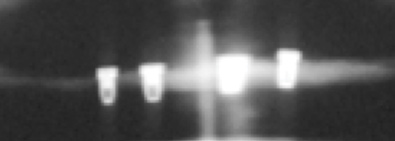

As an alternative to the relatively expensive traditional hybrid restoration that the senior population may perceive as unattainable at their age, an immediate-load all-resin provisional may often be a reasonable option as an entry-level prosthesis. This can serve for extended periods or indefinitely, and when made with a sufficient volume of resin and opposing a light occlusion such as a maxillary denture, it can offer the benefit of fixed retention at a significant reduction in expense (Figure 15 and Figure 16). Technology involving a guided approach for placing three implants universally in the same sites with pre-manufactured, one-size-fits-all bar components in the mandible can now allow placement of a final restoration in one day, again at a significantly reduced cost (Figure 17 and Figure 18).24-26 Both of these fixed options—the resin long-term provisional and the three-implant bridge—are economically comparable to the most commonly considered implant prosthesis for elderly patients, the two-implant overdenture. In contrast to the latter, however, both fixed restorations offer significant advantages in bite force, bone preservation, maintenance, and patient satisfaction that are simply unachievable with the removable implant overdenture prosthesis.27-31

Fig 17. A three-implant fixed bridge may be an immediate-load alternative for a fixed restoration as opposed to a two-implant overdenture. In addition to significant cost reduction due to pre-manufactured components, the final long-term restoration is delivered on the day of surgery.

Figure 17

Fig 18. A three-implant fixed bridge may be an immediate-load alternative for a fixed restoration as opposed to a two-implant overdenture. In addition to significant cost reduction due to pre-manufactured components, the final long-term restoration is delivered on the day of surgery.

Figure 18